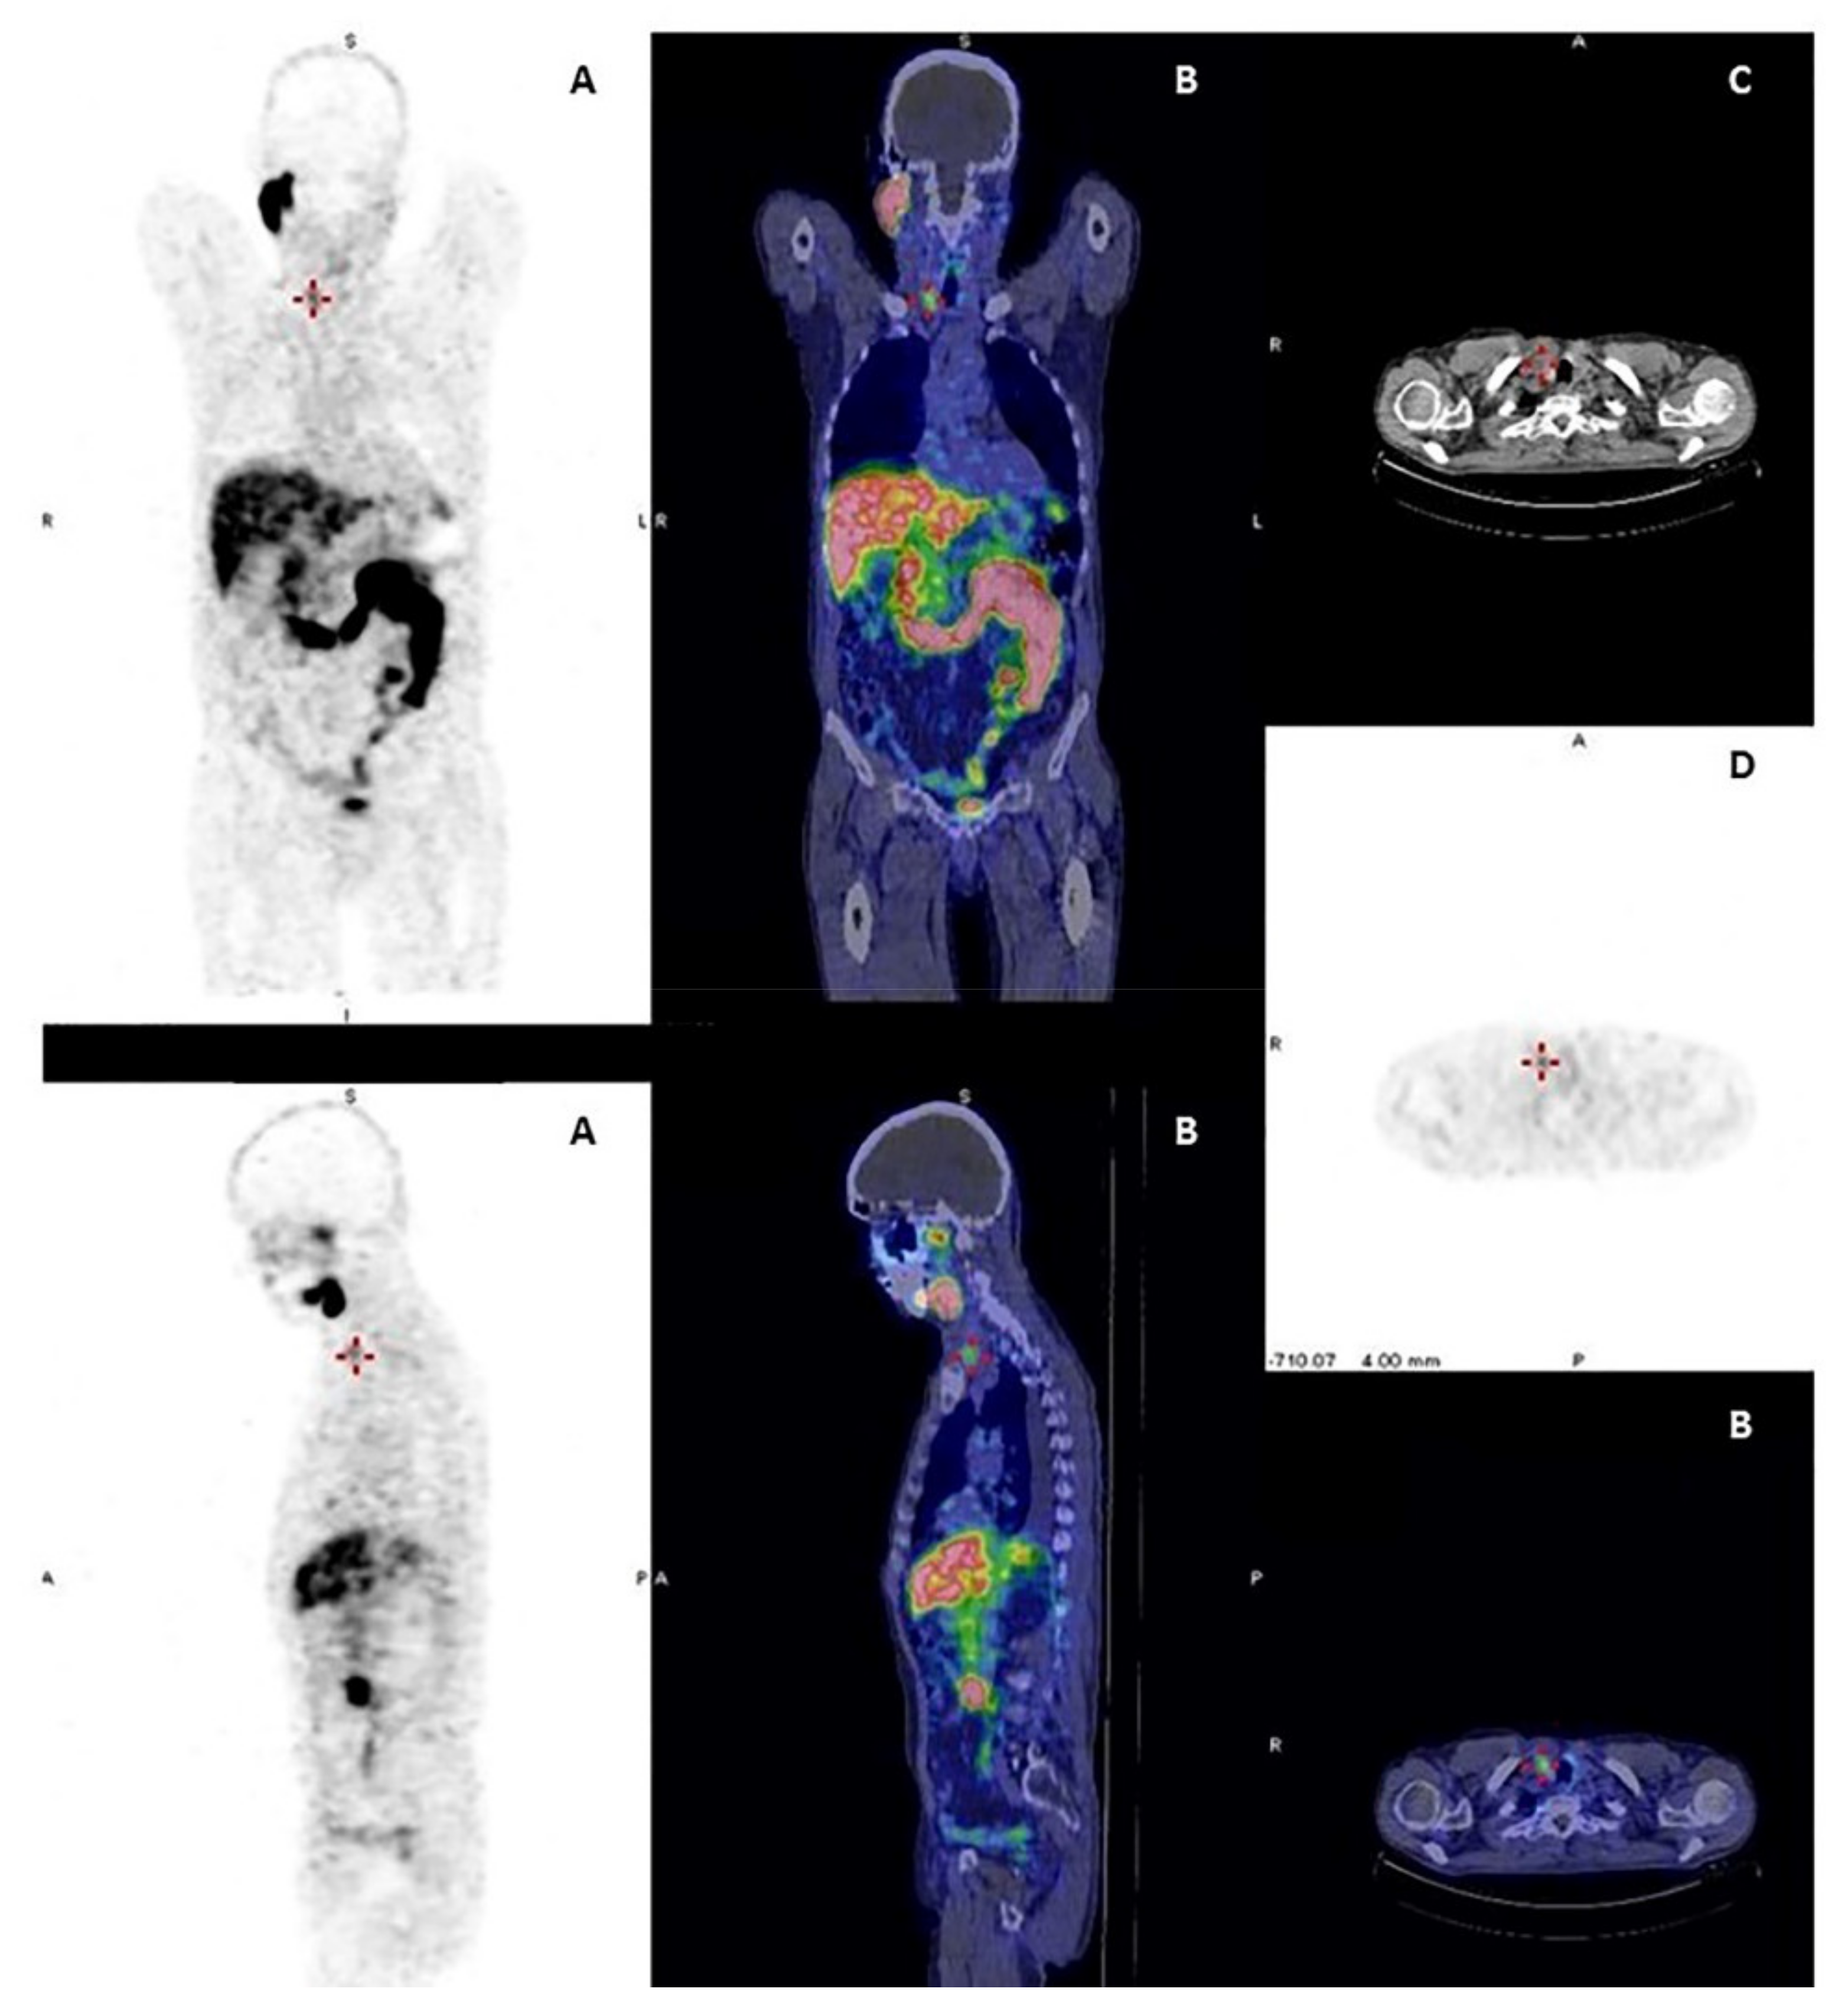

Figure 3.

A 76-year-old patient with prostate cancer and a right thyroid nodule of 15 mm in diameter. Multiple image projections (A), fusion PET-CT images (B), CT images (C) and PET images (D), respectively, of 68Ga-PSMA imaging with high-intensity PSMA accumulation. Fine needle aspiration biopsy of PSMA-avid thyroid lesion was performed revealing an indeterminate cytology. Final histology revealed papillary thyroid cancer.

The prostate-specific membrane antigen (PSMA) is a transmembrane glycoprotein receptor that is highly expressed in prostate carcinoma cells. However, its expression has been associated with neovascular development in several tumors, including DTC [81]. Its expression seems related with a lower differentiation level and more aggressive histology or refractoriness. The 68Ga-PSMA was used in small series of DTC patients with some promising results as a theragnostic radiopharmaceutical, giving the possibility in case of positive imaging results to select DTC patients for 177-Lutetium (177Lu)-PSMA therapy [82]. Recently, two patients underwent (177Lu)-PSMA therapy and achieved a minor tumor response [82]. The agent 2-(3- {1-carboxy-5- [(6- [(18)F] fuoropyridine-3-carbonyl)-amino]-pentyl}-ureido)-pentanedioic acid (DCPyl) labeled with 18F is another PSMA-PET imaging agent with the advantage of imaging obtained with 18F consisting in a potential widely available and easily low cost produced tracer (Figure 3) [43]. 18F-Fluoride has been used for evaluating with PET patients with bone metastases from thyroid cancer in small series of patients, but these lesions are lytic, frequently with a low uptake and this makes their evaluation difficult [83]. This is in accordance with the absence of efficacy of 223Radium in treating bone metastases from DTC [84]. Further studies are needed for evaluating the utility of these tracers in DTC patients.